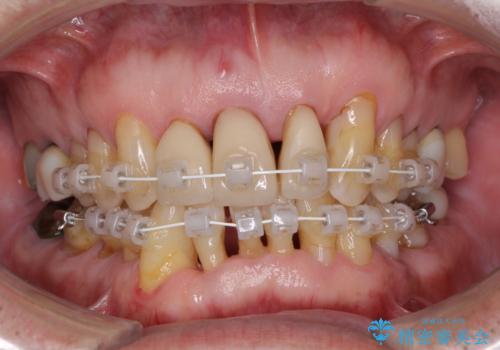

- 上の前歯が痛むとのことで来院された患者様です。

検査を行ったところ、前歯1本は周辺の骨が失われており、抜歯が必要でした。

上顎の奥歯は全体的に歯周ポケットが散見され出血が認められたため、歯周外科処置を行うこととしました。

上の歯は見た目を良くしたいというご希望があったため、歯周外科処置を行った歯についてはセラミッククラウンで補綴することとしました。

また、前歯の部分矯正も希望されたため、歯周外科処置と平行して矯正治療を行うこととしました。